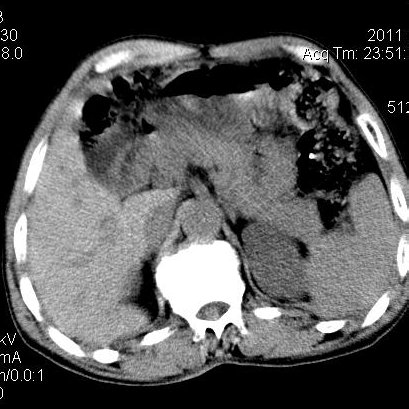

肝左叶发育异常

男性,55岁,骑摩托车摔倒后入院,自述右上腹疼痛

[backcolor=#FF0000]第一次诊断的时候也是这么肯定,可是床旁超声检查并没有发现明显异常,而且患者的一般症状都良好。还好临床只是保守治疗,没有立即手术,第二次复查的时候没有一点变化,又做了MRI检查,没有血肿,

这是一例肝左叶发育异常的,很个性吧~[/backcolor]